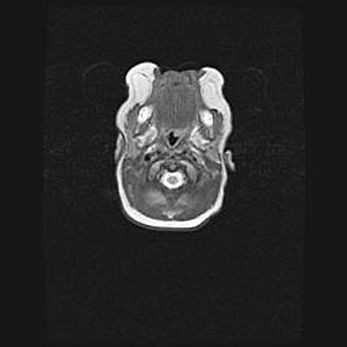

Мальформация Денди-Уокера. Киста задней черепной ямки.

Агенезия мозолистого тела.

Возраст: 2,5 месяца

Вес: 2420 г

Пол: женский

Окружность головы: 37 см

Срок гестации: 32 недели

Мальформация Денди—Уокера — редкий вид патологии ЦНС, представляющий собой врожденный порок развития каудального отдела ствола и червя мозжечка, ведущий к неполному раскрытию срединной (Мажанди) и латеральных (Лушка) апертур IV желудочка мозга. Для этогно синдрома характерна триада симптомов: гипотрофия червя мозжечка и/или полушарий мозжечка, кисты задней черепной ямки, гидроцефалия различной степени. В 70% случаев порок сочетается и с другими аномалиями головного мозга, в частности с агенезией мозолистого тела.